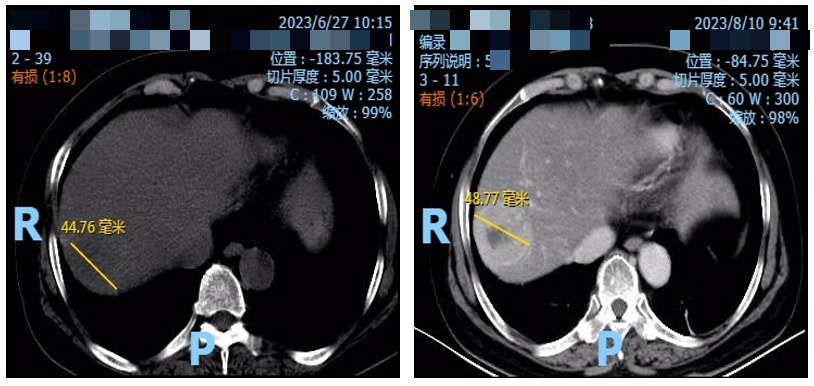

治疗期间定期复查CT示肝脏靶病灶持续缩小。

2024年11月25日复查,CT示肝脏靶病灶缩小至17.05mm(图4),肿瘤标志物也呈持续下降趋势。

图4. 腹部CT检查(2024年11月25日)